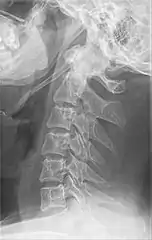

Radiograph, lateral view showing elongated stylohyoid process and stylohyoid ligament ossification

Imaging is important and is diagnostic. Visualizing the styloid process on a CT scan with 3D reconstruction is the suggested imaging technique.[12] The enlarged styloid may be visible on an orthopantogram or a lateral soft tissue X ray of the neck.